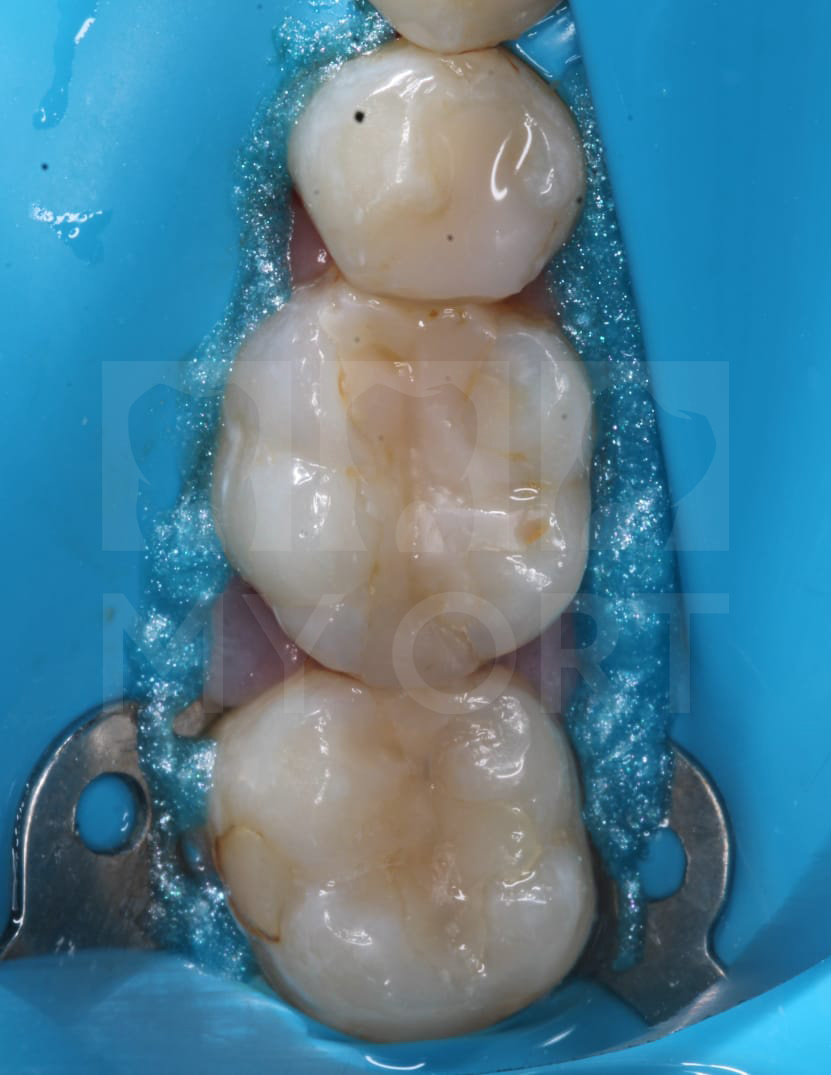

В этой статье я представлю один из клинических случаев, где мы вылечили кариес пациенту и заменили плохо прилегающие пломбы, чтобы под ними в будущем не развился вторичный кариес. На первый взгляд, у пациента все неплохо. Видны устаревшие пломбы, которые уже стали терять плотное прилегание к тканям зубов и могут привести к вторичному кариесу.

На первый взгляд, у пациента все неплохо. Видны устаревшие пломбы, которые уже стали терять плотное прилегание к тканям зубов и могут привести к вторичному кариесу.